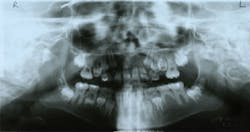

Radiographic Oral Assessment

- Panoramic radiograph (see Figure 9)

- Mandibular right deviation was 1 mm to the left

- Right condyle had a thin, flat appearance

- "Deciduous" teeth present: B, C, H, I, K, L, M, R, S, and T, and permanent teeth present: Nos. 3, 7-10, 14-19, 23-26, and 30

- Slight crowding mandibular anterior teeth

- Small jaw structure on maxilla and mandibular arches (larger permanent teeth than space will allow)

- No. 20 is congenitally missing

- Unerupted teeth: Nos. 1, 2, 4-6, 11-13, 15-18, 21, 22, 27-29, 31, and 32

- Slight deviation of nasal septum

- Normal trabeculation pattern on mandible

- Premature shedding of teeth A and J

- Slight localized horizontal bone loss

- Maxillary sinus was slightly congested (smaller and cloudy on the panoramic radiograph)

Figure 9: Patient Q, panoramic radiograph

On the panoramic radiograph, there was a slight deviation in the nasal septum. This will affect the patient's breathing and complicate her asthma and sinus difficulty. Oxygen or breathing machines may need to be utilized to assist with airway issues.